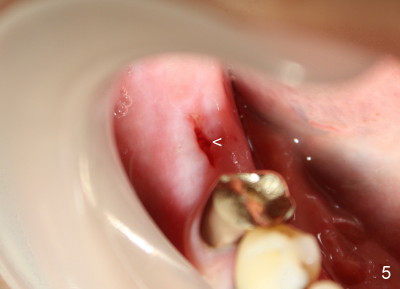

In case that there is an oral infection, submerged implant (Fig.4: I; Bicon 5x8; white line indicates gingival margin) may reduce the chance of pathogen contamination postoperatively. Fig.5 shows slight wound gaping after suture removal, one week postoperatively. In contrast, the implant in Fig.4' (Tatum 6x17) is non-submerged (white line indicates gingival margin). Two week post-operatively, an infection develops buccal to the implant (Fig.5'). Bone loses around the non-submerged implant 1 month after placement (Fig.4"). Finally the implant has to be removed. Return How to Avoid Post-implant Infection